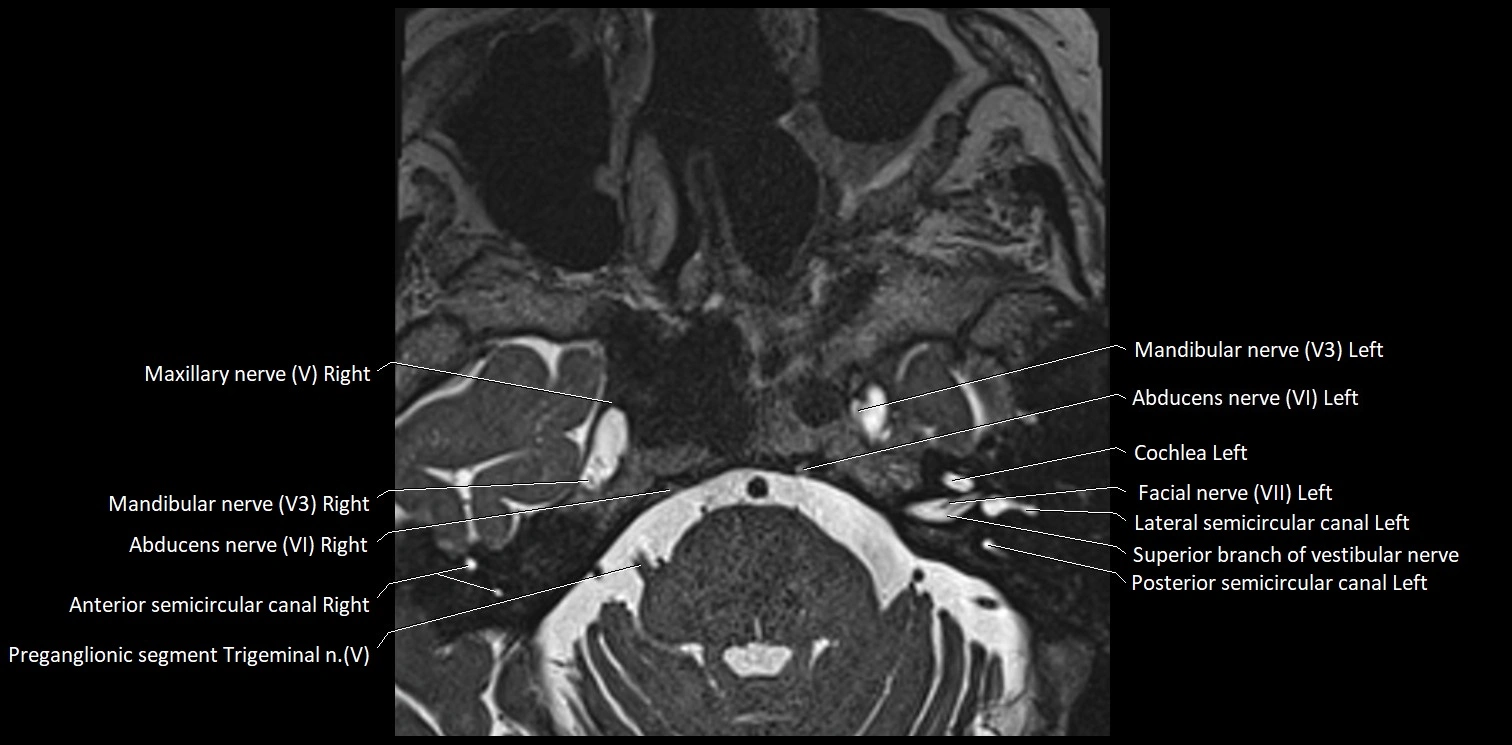

MRI Appearance

• The abducens nerve is a small, thin, linear structure

• Best visualized on high-resolution T2-weighted 3D MRI sequences (e.g., FIESTA or CISS)

• Seen as a hypointense (dark) line running from the brainstem at the pontomedullary junction, traversing the prepontine cistern, and entering Dorello’s canal under the petrosphenoidal ligament, then into the cavernous sinus, and finally the orbit

• May be challenging to visualize in standard MRI due to its small size

• Pathology may be inferred by absence, displacement, or enhancement of the nerve